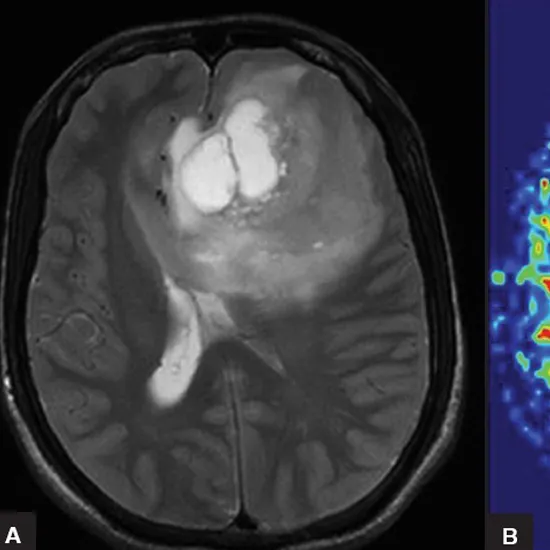

An MRI Brain Perfusion is a type of brain test that reveals the amount of blood taken up in certain areas of your brain using a particular MRI sequence. It provides information on the functioning of your brain.

The MRI Brain Perfusion is done to make assessment of acute stroke or intracranial tumors. It is a promising imagining tool that is used to evaluate stroke, brain tumors, and patients with neurodegenerative diseases.

Brain perfusion scan is an imaging technique that helps in evaluating the blood flow amount that is flowing to various parts of the brain. This information is collected with the help of MRI sequencing. MRI sequencing uses magnetic fields for the generation of scan images.

MRI brain perfusion tests are done post-stroke or tumors intracranial evidence. It helps in evaluating the blood flow to the brain, reduced blood flow can often lead to disorders causing stroke or seizures and other disorders.

The diagnostic accuracy of the MRI brain perfusion scan is sufficiently high to help diagnose blood flow and perfusion values. The test has a sensitivity of 74% and a specificity of 92%.